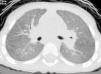

At the age of 30 months (when the last episode had occurred 2 months previously), a chest X-ray was obtained during a stable period of good health in the twin with the more severe clinical history, and persistent interstitial-alveolar involvement was observed; a high resolution CT scan (HRCT) revealed ground-glass opacification of the image, with an interstitial pattern and fine nodules (Fig. 1).